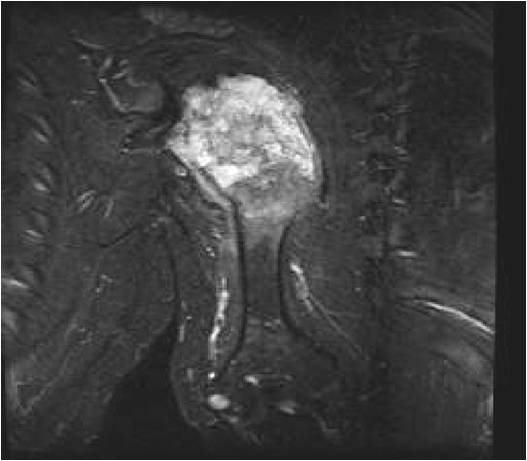

MRI:

- Lobulated margin (Lobular Growth Pattern)

- T2 Weighted Images: High Signal Intensity

- High water content shows as high signal on T2 weighted images

- Calcifications will be low signal

- Marked increased intensity long TR images

T2: High Signal No Soft Tissue Component